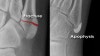

X-ray : 제5중족골 골절(Avulsion fracture of Plantar fascia)

X-ray : 제5중족골 골절(Avulsion fracture of peroneus brevis tendon)

Left image : The fracture line passes transversely across the bone.

Right image : A normal unfused 5th metatarsal base apophysis is aligned more longitudinally along the bone.

Developing apophysis는 시상면 방향으로 된 성장판을 가지는데, 골화 중심이 종축 방향이기 때문